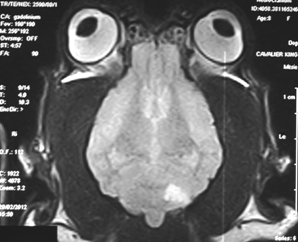

Ischemic stroke (or cerebellar ischemic stroke) is a sudden blockage of the blood flow to an area of the cerebellum of the brain caused either by a blood clot.* The blockage deprives the delivery of oxygen to that portion of the brain, creating a dead tissue lesion, typically wedge-shaped (see MRI image at right), called a cerebellar infarct. This usually results in the loss of some neurological function which had been controlled by the affected area of the brain.

(The image at right is an MRI scan of a CKCS skull, showing a wedge-shaped cerebellar infarct at lower right of the brain. Image from The Downs Veterinary Practice.)

anesthetized and an MRI of the brain was performed. A large, left-sided,

rostral cerebellar wedge-shaped region was hypointense on T1-weighted

images and hyperintense on T2-weighted images. ... Figure 2 [right]

shows the hyperintense lesion on a T2-weighted image in axial